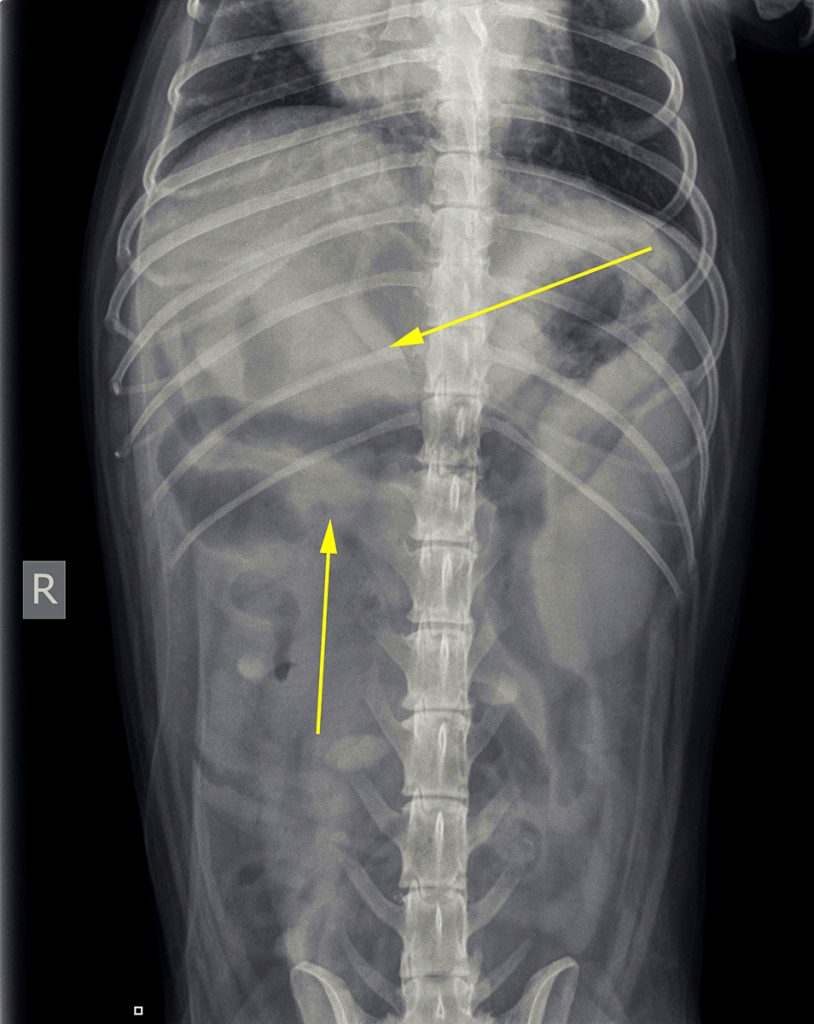

Op basis van deze afwijkingen is er toen voor gekozen om röntgenfoto’s te maken.

De belangrijkste afwijkingen die op de röntgenfoto’s te zien waren: minder contrast dan we gebruikelijk zien en mogelijk een structuur. Er was echter geen aanwijzing voor een verstopping.